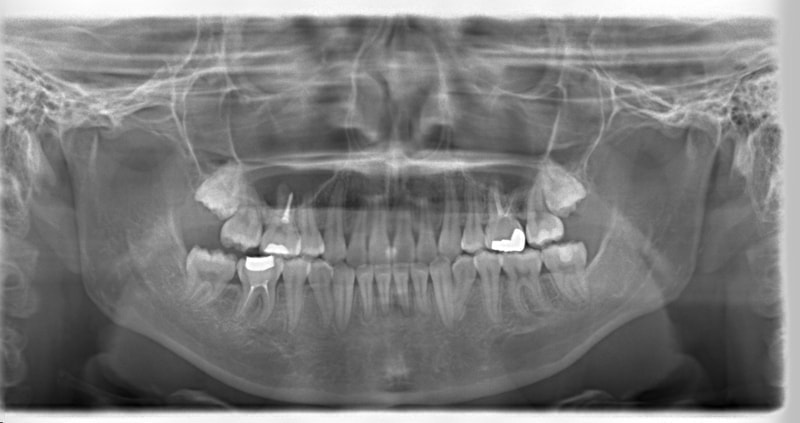

上顎前突+右下7番重度埋伏

(右下7番目の永久歯が下顎の中に埋まったまま、親知らずが上に乗っている)

治療法:フルパッシブブラケット:T21

解説:右下7番を抜歯し、右下8番を開窓牽引しました。近年、顎が退化しており、歯の大きさとの不調和がどんどん強くなりつつあります。2018年の矯正学会でも、本症例と同様の下顎7番8番の問題ケースが講演で紹介されておりました。こうなる前に、先手を打ちたいものです。小児の間に先行治療できるのがベストですので、お子様が6才になったら矯正専門医院に初診相談に行くようにしましょう。やる必要があるかどうかを聞きに行くのです。

治療前